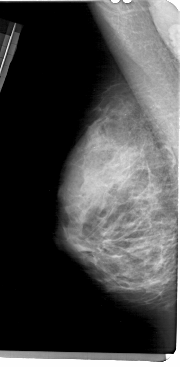

A_1364_1.RIGHT_MLO

RIGHT_MLO LINES 5491 PIXELS_PER_LINE 2581 BITS_PER_PIXEL 12 RESOLUTION 43.5 OVERLAY